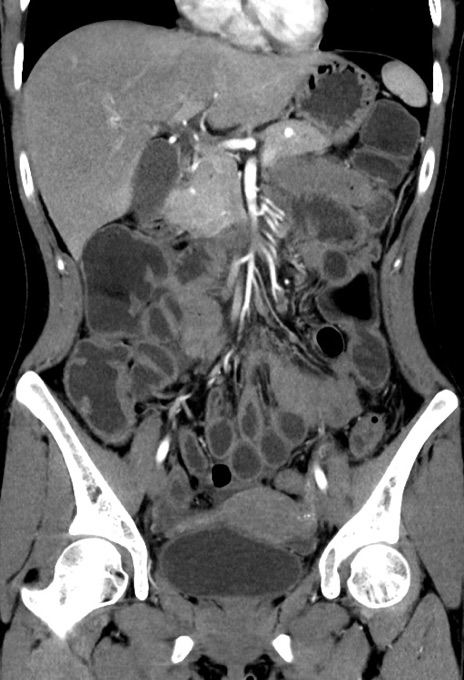

症例17(冠状断像)

【症例】20歳代女性

【主訴】嘔吐、下腹部痛

【現病歴】昨日夕食後に嘔吐し下腹部痛が出現。本日になっても嘔吐持続し改善しないため来院。

【身体所見】意識清明、BT 37.2℃、BP 108/67mmHg、腹部:平坦、やや硬、下腹部正中から右にかけて圧痛あり、反跳痛軽度あり、tapping pain(+)。

【データ】WBC 13600、CRP 14.94